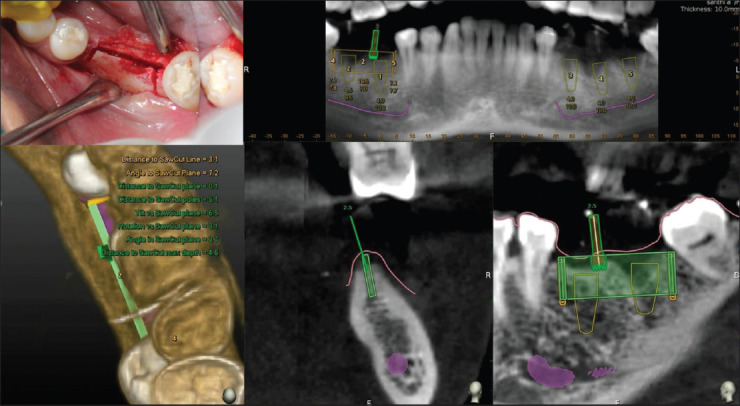

Conventional alveolar ridge splitting (ARS) technique involves a significant risk which may prove problematic. This case report presents the first documented application of dynamic navigation system (DNS)-guided ARS, demonstrating a precise approach to implant placement in a challenging anatomical scenario. A 37-year-old partially edentulous patient presented with missing mandibular posterior teeth. Clinical examination revealed a deficient alveolar ridge. Cone-beam computed tomography evaluation showed a Siebert's Class I resorbed ridge with 2.5 mm width and bone density ranging from 870 to 1040 Hounsfield Units in the #46 and #47 regions. Creating and designing three-dimensional virtual guide slits and implant planning using DNS were done in patient with insufficient bone width in the mandibular molar region. Piezoelectric ARS, osteotomy preparation with implant placement was done. 0.70 and 0.26 mm deviations at #46 and 0.50 and 0.01 mm deviations at #47 were observed at implant entry and implant apex, respectively. The angular deviations were optimal. ARS using real-time navigation appears to be an efficient and promising technique.